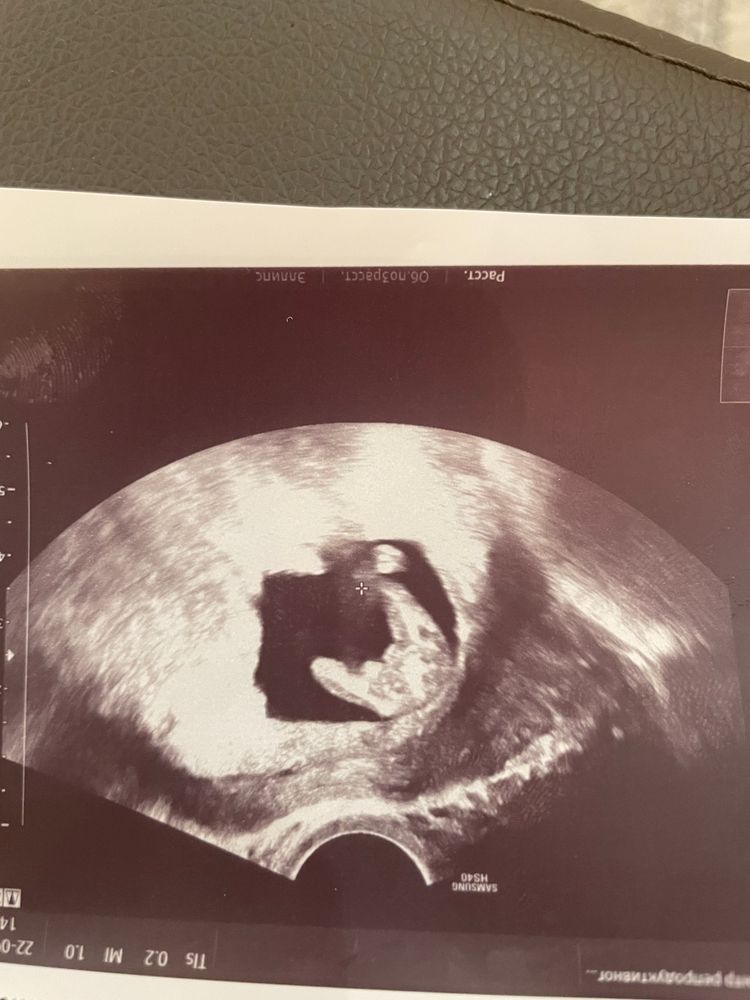

В 14-15 недель дали это фото , мужу говорит передайте посидите вечер погадайте 😂😂😂это вид снизу , на след день написала мне в телеграмме что девочка ))) но я вот так и не поняла по фото , у меня вообще с этими узи туго мне говорят видите там это это я в упор смотрю и вижу расплывчатые пятна какие то , не стараюсь даже уже присматриваться